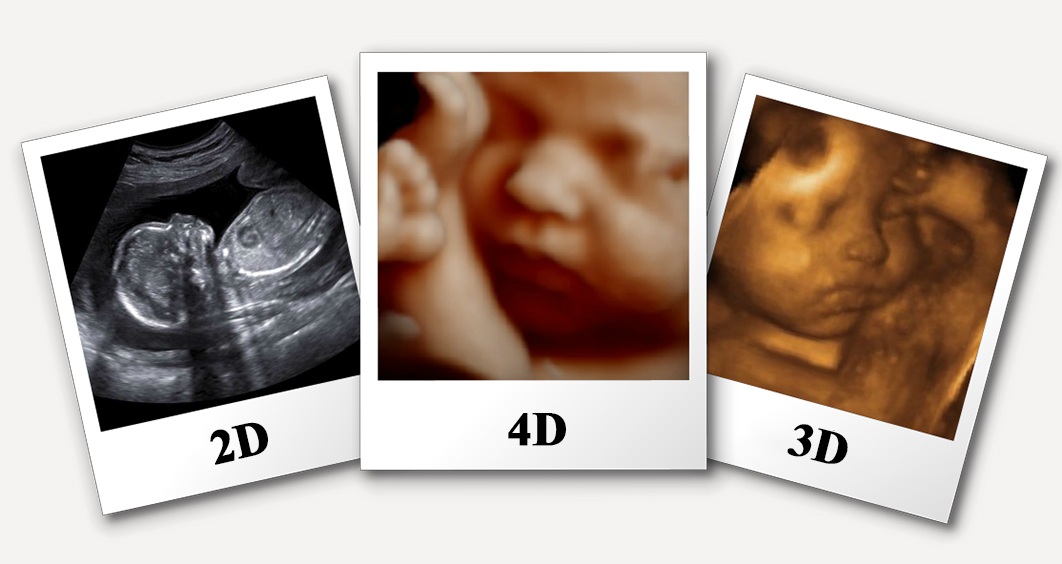

A 4D sonography centre in Gujarat resembles a 3D ultrasound, nonetheless, the image shows advancement like a video would. So in a 4D ultrasound picture, you'd see your youngster finishing things continuously. With 4D imaging, the signs delivered off the machine are constant, giving gatekeepers a point of view on their adolescent consistently, complete with looks and body advancement.

3D and 4D imaging gatherings can require an hour or longer, yet under 30 minutes of that time will be taken up by the genuine ultrasound. How far along would it be prudent for me to be before I have a 4D ultrasound? In case you expect to have quite recently a solitary 4D ultrasound meeting, we would propose having the ultrasound performed between the 26th and 34th seven-day stretch of the pregnancy. 4D sonography centre in Gujarat regardless, remarkable photos of your kid can be gotten at whatever point after around 22 weeks of pregnancy.